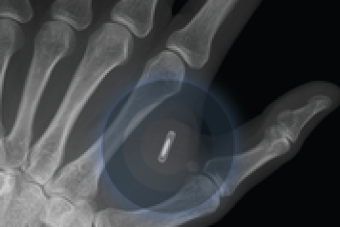

Swedish employees agree to free microchip implants designed for office work

150 of the company's "young" workforce

RFID chips are roughly the size of a grain of rice